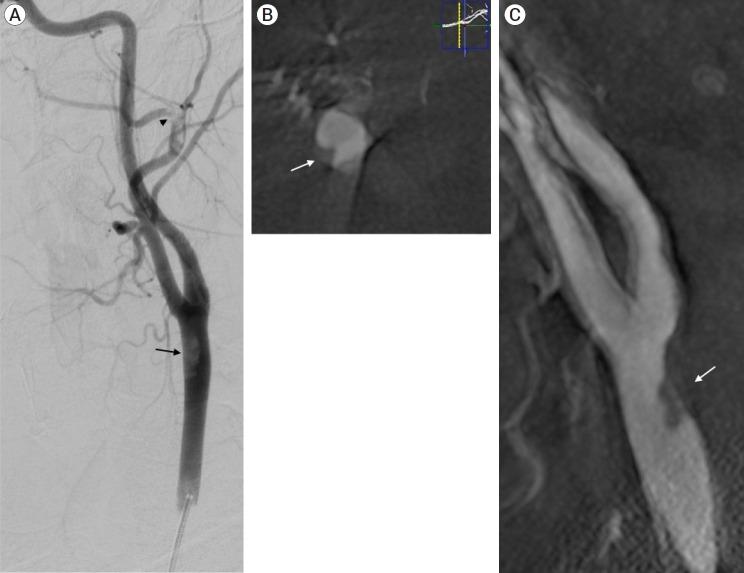

The carotid web (CW), an intimal variant of fibromuscular dysplasia (FMD), is recognized as a cause of stroke and with a high-risk of stroke recurrence. Other names are carotid-bulb atypical FMD, carotid (bulb) diaphragms and it is described like a shelf of tissue from the posterior wall of the carotid bulb. Here we present a case of a young patient with recurrent stroke, with no other risk factors that was diagnosed with a common CW.

颈动脉纤维肌性发育不良内膜变异型(CW)被认为是中风的一个病因,且中风复发风险高。其他名称有颈动脉球部非典型纤维肌性发育不良、颈动脉(球部)隔膜,它被描述为从颈动脉球后壁突出的一层组织。在此,我们报告一例年轻的复发性中风患者,该患者无其他风险因素,被诊断为常见的CW。